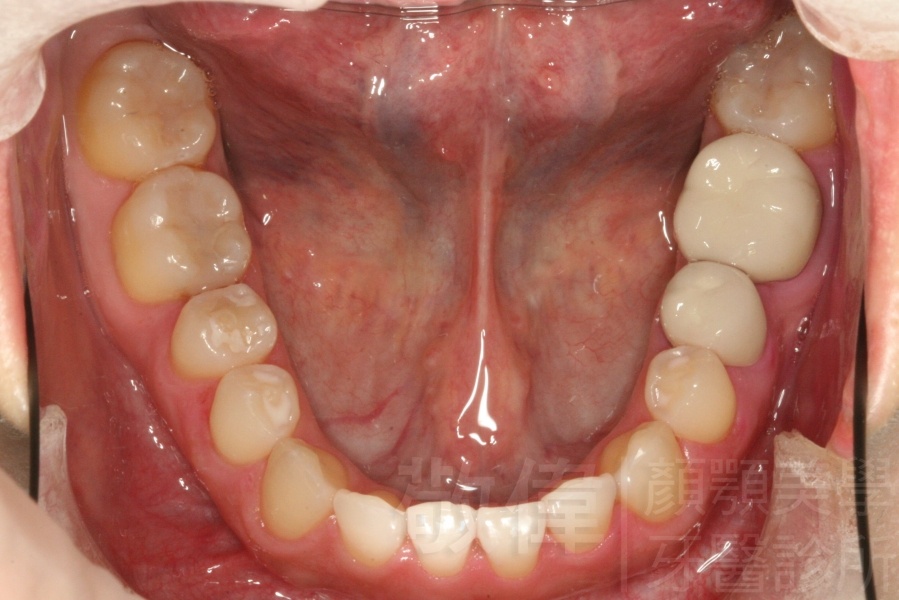

變臉矯正,原來戽斗妹跟大歪臉變成自信正妹

經由本院3D數影X光影像儀分析、與3D齒顎顏矯正技術,再配合口腔顎面正顎專科醫師施以正顎手術治療,雙方共同合作,使患者臉部外觀有很好的改善,大歪變小歪,產生了天南地北的大改變,她的人生也整個變得不一樣。

因為矯正與正顎手術的配合,使「戽斗妹」變成了「陽光正妹」,完全的改變了她的人生,在面對各種場合、與人交際都散發出自信微笑。所以,奉勸家長,如果小朋友有臉顎畸型的問題,應該考慮配合做這種簡單、安全、有效的正顎手術。